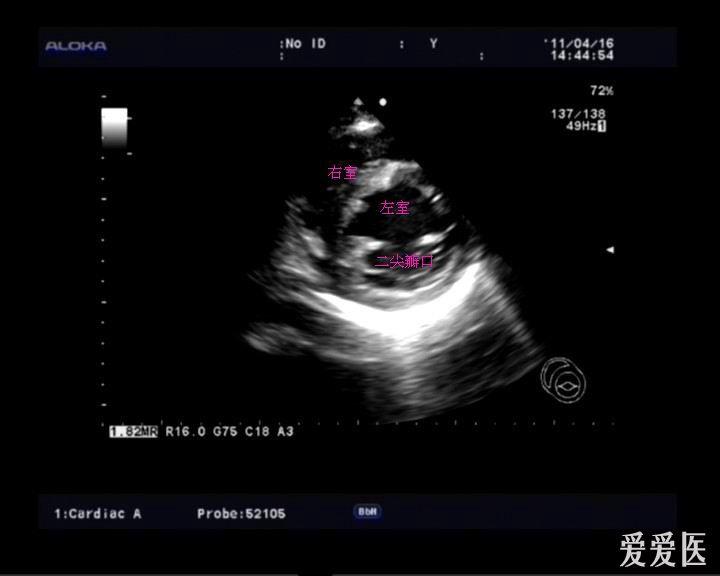

复习常用心脏切面 - 超声医学讨论版 - 爱爱医医学论坛